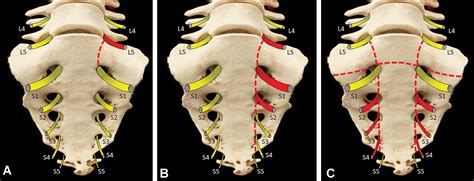

The sacrum is a triangular-shaped bone formed by the fusion of five sacral vertebrae. The "ala" (Latin for "wing") refers to the broad, flared sections on either side of the sacrum. These wings articulate with the ilium of the pelvis to form the sacroiliac joints. When an Ala of sacrum fracture occurs, it often results from high-energy trauma, though it can also be seen in patients with compromised bone density, such as those with osteoporosis.

The proximity of the sacral ala to the sacral nerve roots makes these fractures particularly sensitive. Injury to this area can potentially affect lower limb function, bowel or bladder control, and overall mobility. Proper classification of the fracture, often determined through medical imaging, is the first step in determining whether a conservative or surgical approach is necessary.